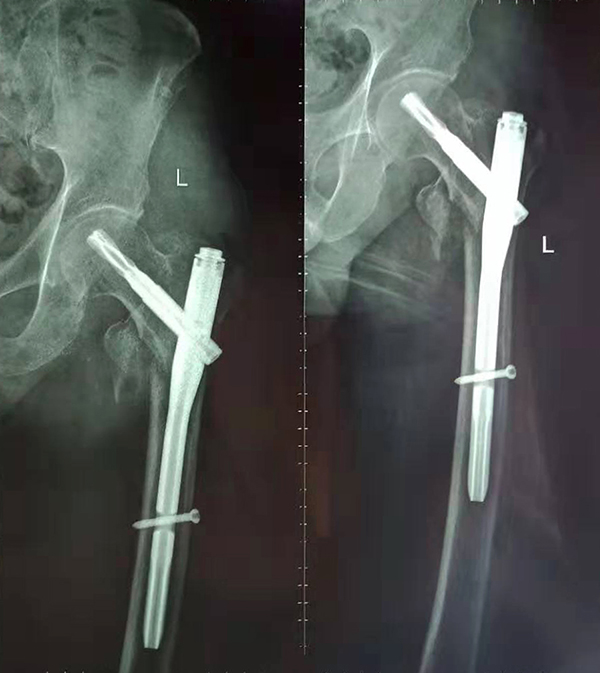

經(jīng)術(shù)前仔細(xì)的檢查和評估,與張爺爺家屬充分溝通,決定了實施閉合復(fù)位PFNA內(nèi)固定術(shù)的方案,劉鴻程主任說到,該術(shù)式的創(chuàng)傷小、出血少,適合骨質(zhì)疏松病人,術(shù)后解除患者疼痛,可以早期開始活動,便于護理。

手術(shù)后

9月10日上午,骨科順利完成張爺爺?shù)淖蠊晒谴致¢g骨折髓內(nèi)釘內(nèi)固定術(shù)。手術(shù)過程中麻醉平穩(wěn),術(shù)中出血量少,骨折手術(shù)時間持續(xù)一個多小時。